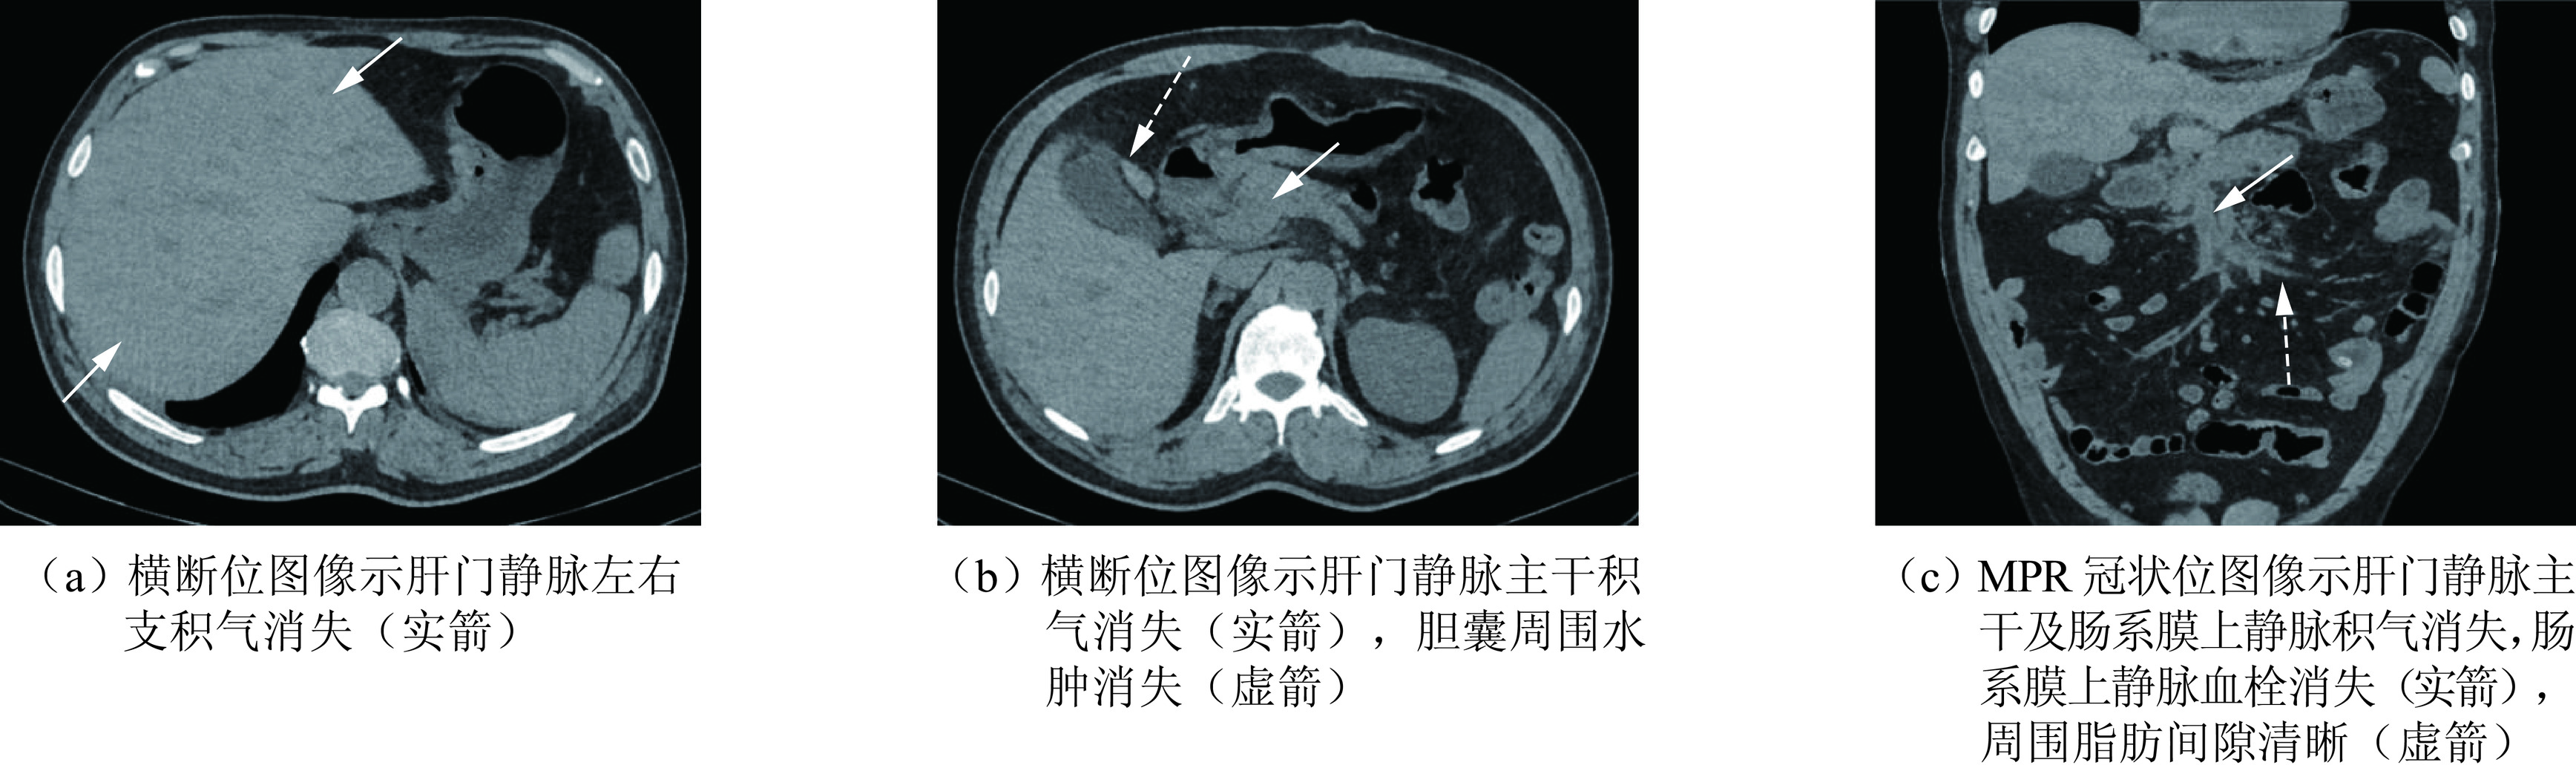

2.3 术后复查腹部MSCT平扫所见

空肠上段部分切除术后。肝门静脉主干、肝内门静脉分支及肠系膜上静脉积气消失、肠系膜上静脉血栓消失。胆囊壁增厚好转,胆囊窝及肝门区积液消失,肠系膜脂肪间隙清晰(图7)。

回顾本病例,患者以无明显诱因发热、持续性腹痛入院,我们分析患者出现发热腹痛的原因可能是空肠憩室破口与肠系膜静脉相通后,导致肠系膜上静脉内血栓形成,造成肠系膜上静脉发生炎症反应,进而进展为肠系膜上静脉周围腹膜炎所致。CPR重建图像(图3)显示肠系膜上静脉周围脂肪间隙浑浊,符合腹膜炎改变,也印证了我们的推测。MSCT可见空肠憩室穿孔并肝门静脉积气、肠系膜上静脉血栓,与术中所见及病理诊断相符。MSCT通过MPR多角度重建技术能清晰显示空肠憩室穿孔并与肠系膜上静脉相通的确切位置,通过MSCT血管追踪重建技术可准确显示肝门静脉积气与空肠憩室关系,从而找到了了肝门静脉内积气的病因,为临床诊治提供了重要信息。增强MSCT通过MPR重建及血管追踪重建技术的应用确切显示了肠系膜上静脉内存在血栓的情况,这与手术中所见及病理相吻合。日后工作中如再遇到类似病例,我们计划对患者进行CT小肠造影(CTE)检查,CTE作为一种无创性检查手段,可以同时观察肠内、外病变的情况[15],有助于清晰显示空肠憩室。